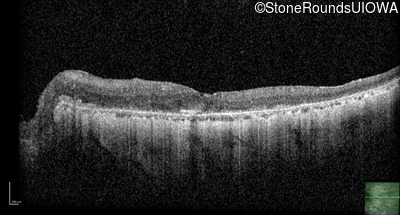

Optical Coherence Tomography - Right - 20/25 -1

Exemplar / OCT Stack